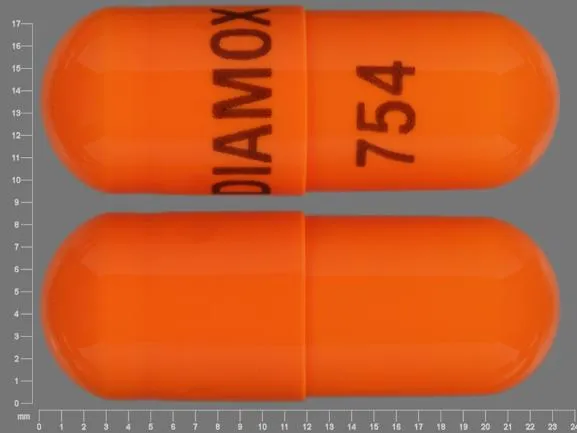

Podemos utilizar acetazolamida nos pacientes em diálise? Muito cuidado!

Valkercyo Feitosa

2 anos atrás